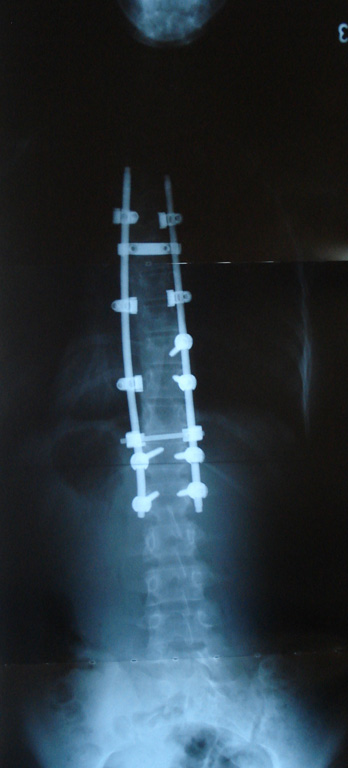

Grafilerle Skolyoz